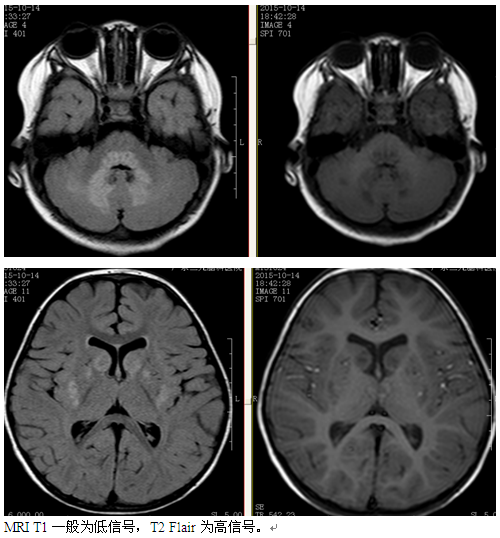

辅助检查:2015年10月13日头颅MRI平扫检查报告:双侧基底节尾状核、豆状核、中脑、双侧丘脑、四脑室周围及小脑半球齿状核周围多发病灶,考虑代谢性疾病可能,以肝豆状核变性可能性大,建议实验室进一步检查。视频脑电图报告:弥漫性慢波增多。线粒体疾病核基因PANEL检测示:患者SURF1基因发现的复合杂合变异分别遗传自受检者父母,父母均为杂合子,符合常染色体隐性遗传方式。(详细见下图)

影像学特点:侧苍白球及导水管周围病变,还可累计丘脑、齿状核、大脑、小脑白质、脊髓、脑皮质,为对称分布,早期肿胀,晚期萎缩。CT平扫为低密度影,一般无强化。MRI T1一般为低信号,T2flair为高信号。慢性期病变可吸收后遗留囊状软化灶,DWI急性扩散期受限,增强后一般强化,MRS显示Cho、Lac升高。